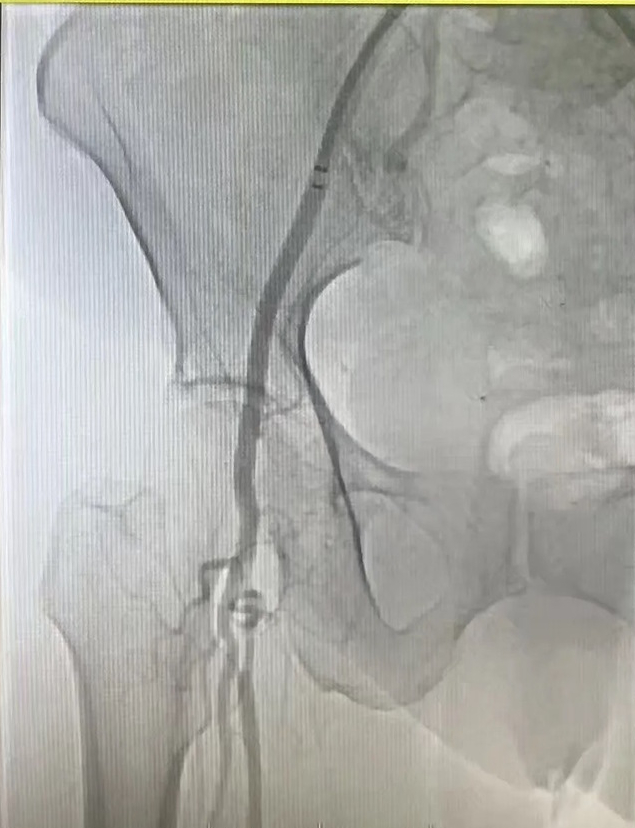

入院后,济南市南山人民医院血管外科团队迅速完善术前检查,为手术做好充分准备。术中,通过造影技术清晰显示患者股动脉栓塞部位及程度,证实了急性股动脉栓塞的诊断。医护团队采用经皮股浅动脉吸栓治疗方案,精准清除血栓,恢复下肢血流。

手术过程顺利,经皮股浅动脉吸栓治疗效果显著,患者下肢疼痛症状明显缓解,血流恢复正常。术后恢复良好,有效避免了因栓塞导致的肢体坏死等严重并发症。